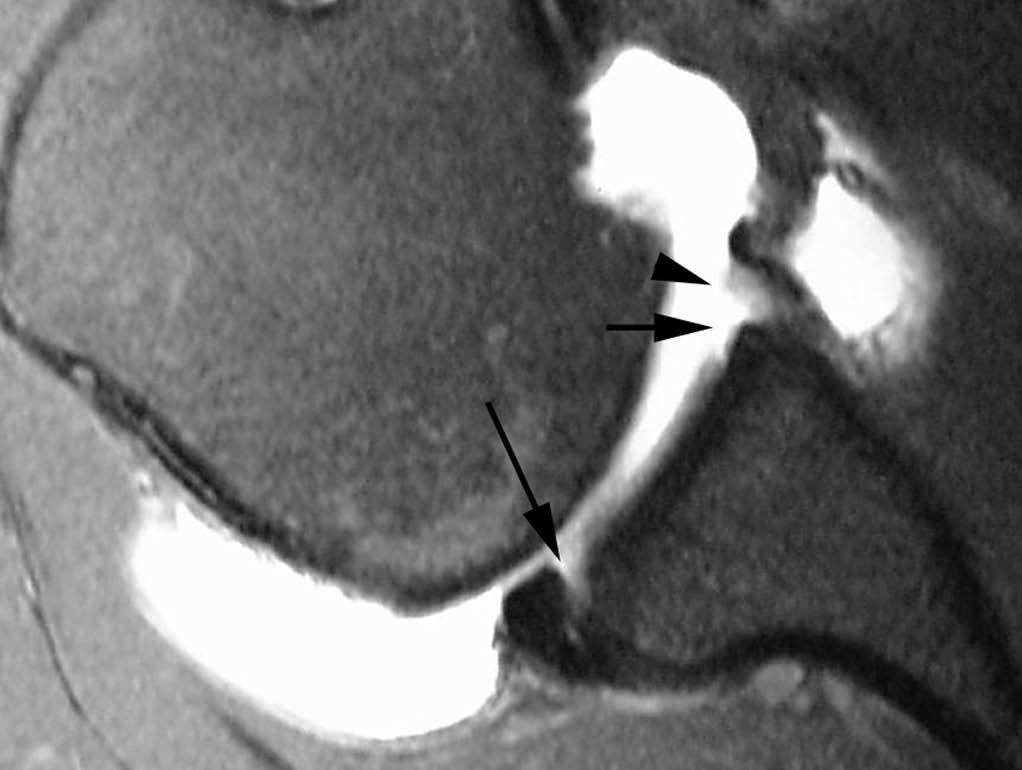

ALPSA (anterior labroliamentous periosteal avulsion)

Al igual que en el apartado anterior, existe también una separación de LG junto con la cápsula y el periostio, pero a diferencia de las lesiones de Bankart o Perthes, el LG se desplaza hacia dentro, por detrás del borde de la glenoides18 (fig. 12). La lesión de ALPSA puede cicatrizar por sinovialización (fig. 12), pero continúa siendo de carácter inestable.

Fig. 12.--ALPSA (anterior labroliamentous periosteal avulsion) agudo (A) y crónico (B). Nótese la separación del labio glenoideo y su desplazamiento posterior y medial por detrás del reborde glenoideo (flecha en A). En una fase crónica el labio glenoideo no se distingue como una estructura separada, sino como un engrosamiento de la unión entre el labio, la cápsula y el periostio (flecha en B).